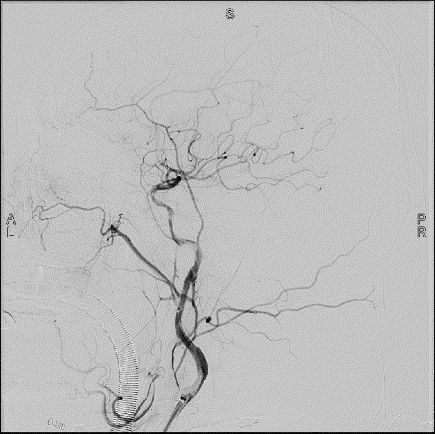

近日,喀什地区第二人民医院(以下简称“喀什二院”)神经内科介入团队完成了医院首例颈动脉长节段非急性闭塞开通术,开通了患者左侧超10厘米长的闭塞颈内动脉,术后患者恢复良好,标志着喀什二院在神经介入技术领域又一次取得突破性进展。

术前造影

入院后完善相关检查和评估,主治医生李红梅发现其左侧颈内动脉闭塞节段超过10 厘米,开通难度非常大,风险也较高。颈动脉闭塞根据发病时间不同分为急性闭塞(闭塞<24小时)、非急性闭塞(闭塞≤1个月)和慢性闭塞(>1个月)。颈动脉是脑部血液的主要供应动脉之一,患者如果缺乏良好侧支代偿将面临极高的卒中复发风险。

由于患者的左侧大脑半球的血液代偿体系建立不好,处于严重低灌注状态,导致脑供血不足,存在较高的脑梗死复发风险,且患者逐步出现认知功能减退的现象。面对这种情况,第十一批上海援疆专家、喀什二院神经内科主任王子高带领团队精心制定手术方案,决定实施左侧颈内动脉闭塞开通术。长节段颈内动脉闭塞开通术手术难度大,对术者要求极高,不仅需要具有娴熟的微导丝、微导管操控技能,更需要有坚持不懈的耐心和应对各种并发症,处变不惊的能力。在完善相关检查及充分术前准备后,王子高带领神经内科介入团队在全麻下为该患者实施了左侧颈内动脉闭塞开通术,历时3个小时,该患者左侧颈内动脉实现完全再通,术后状态良好,患者阿先生说:“我现在头也不昏了,眼睛看东西也更亮了!”